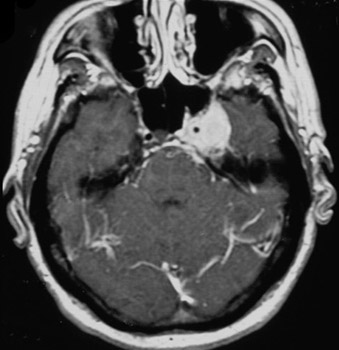

Hemorragia do tronco encefálico no mesencéfalo estendida de uma hemorragia hipertensiva na ponte

Do acervo pessoal de G. Bryan Young, MD; usado com permissão